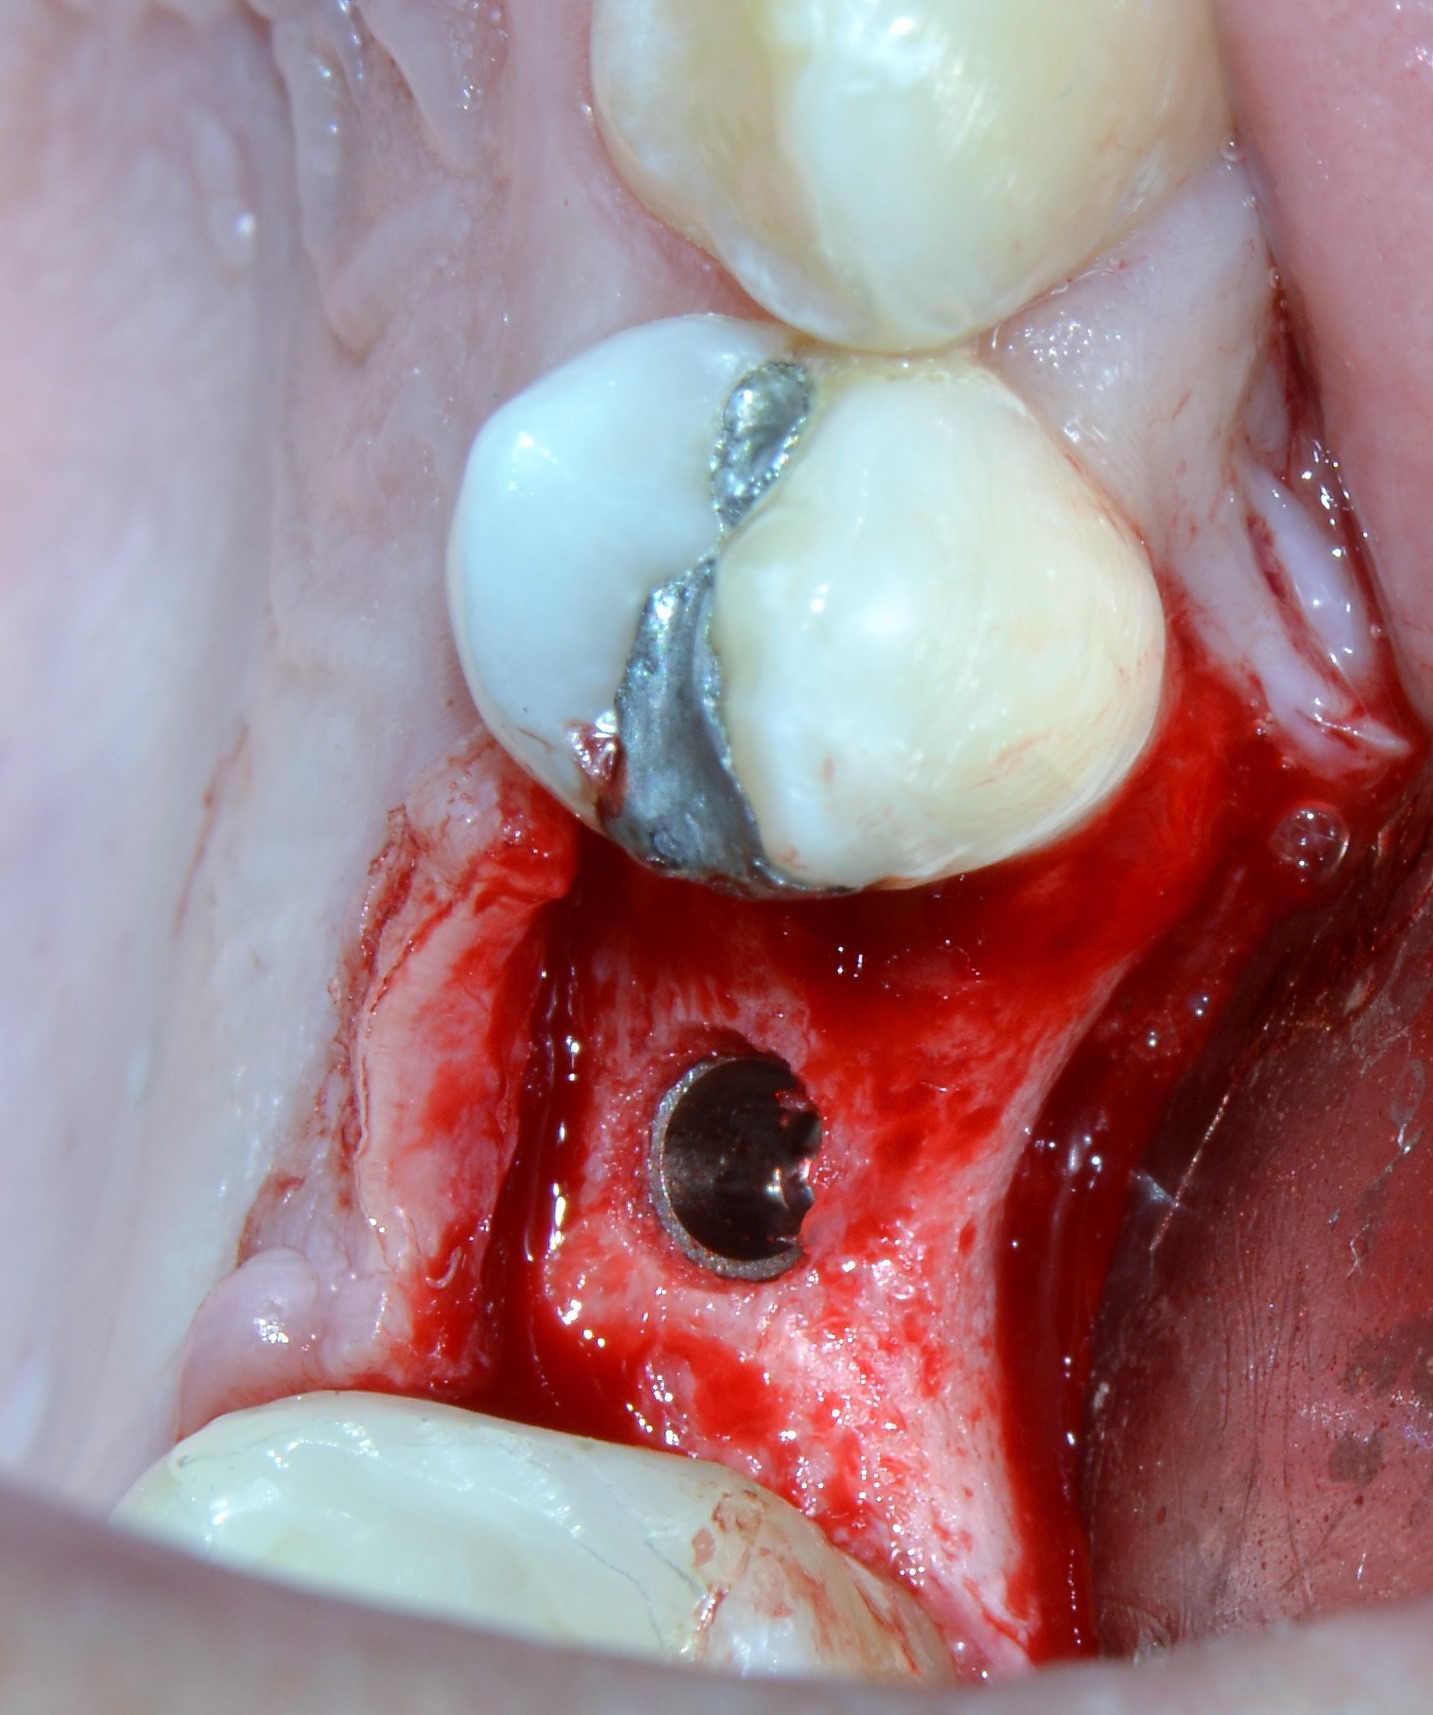

Em seguida, foi realizada uma incisão intrassulcular ao redor da raiz residual do elemento dental, luxação e remoção da raiz dental (Figura 2).

Figura 2: Exodontia da raiz